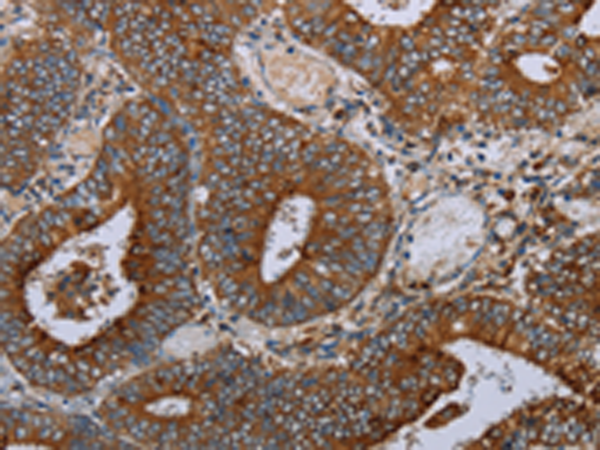

分类: 科研抗体货号: P04091别名: MEK2, MKK2, MAPKK2, PRKMK2应用: WB,IHC反应种属: Human, Mouse, Rat